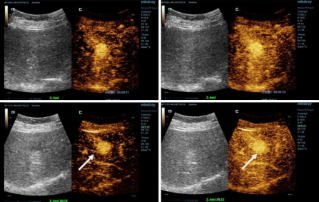

![more-precise-diagnoses-with-hifr-ceus.thumb.319.319 Precyzyjna diagnostyka dzi?ki funkcji HiFR CEUS]() Precyzyjna diagnostyka dzi?ki funkcji HiFR CEUSBadania ultrasonograficzne z kontrastem (Contrast-enhanced ultrasound - CEUS) zyskuj? na popularno?ci, a dzi?ki dynamicznie rozwijaj?cej si? technologii, jako?? obrazu nieustannie si? podnosi. Do takich rozwi?za≈Д nale?y USG z kontrastem o wysokiej cz?stotliwo?ci od?wie?ania (HiFR CEUS), kt√≥re mo?e wygenerowa? do dziesi?ciu razy wi?cej obraz√≥w ni? konwencjonalna ultrasonografia - w tym samym czasie.Ultrasonografia | Obrazowanie og√≥lne 2023-02-16

Precyzyjna diagnostyka dzi?ki funkcji HiFR CEUSBadania ultrasonograficzne z kontrastem (Contrast-enhanced ultrasound - CEUS) zyskuj? na popularno?ci, a dzi?ki dynamicznie rozwijaj?cej si? technologii, jako?? obrazu nieustannie si? podnosi. Do takich rozwi?za≈Д nale?y USG z kontrastem o wysokiej cz?stotliwo?ci od?wie?ania (HiFR CEUS), kt√≥re mo?e wygenerowa? do dziesi?ciu razy wi?cej obraz√≥w ni? konwencjonalna ultrasonografia - w tym samym czasie.Ultrasonografia | Obrazowanie og√≥lne 2023-02-16 -